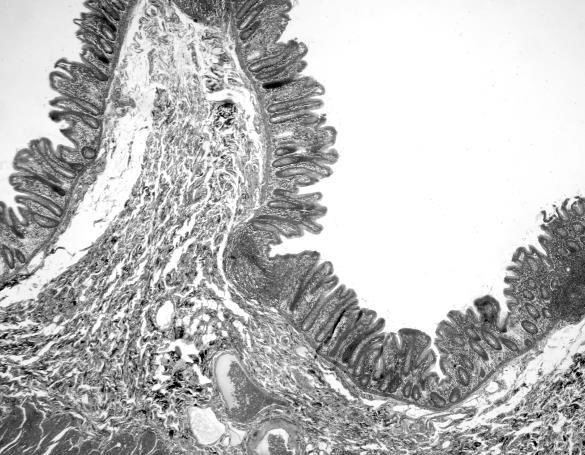

Иллюстрация к книге — Взламывая анатомию [image31.jpg]

Эпителиальные клетки, которые выстилают стенки кишечника, называются слизистой оболочкой, или мукозой.